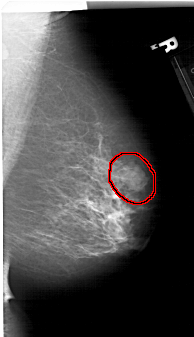

FILE: A_1411_1.RIGHT_MLO.OVERLAY

TOTAL_ABNORMALITIES 1

ABNORMALITY 1

LESION_TYPE MASS SHAPE LOBULATED MARGINS MICROLOBULATED

ASSESSMENT 4

SUBTLETY 4

PATHOLOGY BENIGN

TOTAL_OUTLINES 1

BOUNDARY